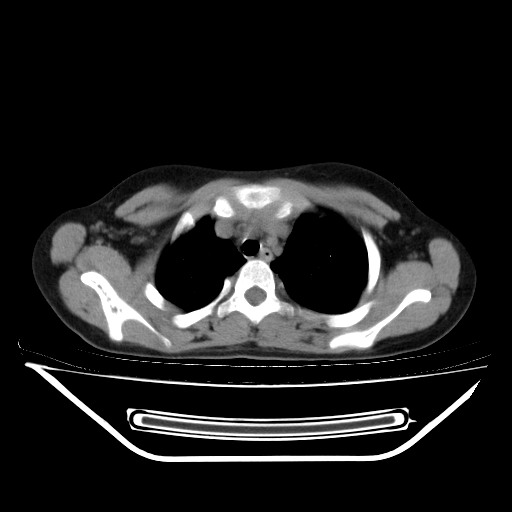

女,12岁,前期发热,咳嗽,无痰,经头孢抗炎无效。ct右肺上叶实变影.5天后公布病理结果。以下是2010-2-13ct片

左前上纵膈可见大块影,与大血管关系密切,邻近肺少许炎症,考虑左前上纵膈占位,胸腺瘤或畸胎瘤,并左上肺膨胀不全。

经过胸部穿刺活检为支原体感染。以下示抗支原体感染30天后所见,病灶明显缩小,临床症状消失: